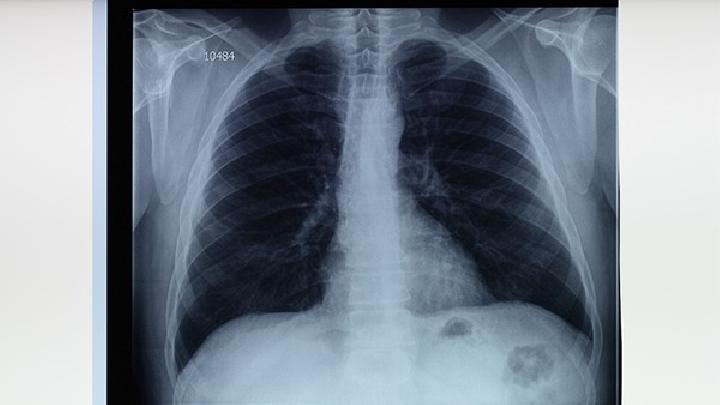

尘肺病的并发症是什么?我相信很多人都想知道这个问题,尤其是那些患有这种疾病的人。毕竟,一种疾病已经足够了。如果有几种疾病,我不知道会发生什么。事实上,尘肺病是由于呼吸系统防御能力的降低,免疫力不同程度地降低,疾病也随之而来。接下来,让我们来看看并发症。

1.呼吸系统感染 主要是肺部感染,是尘肺患者常见的并发症。

2.自发性气胸 很少见。为肺组织和脏胸膜破裂,空气进入胸膜形成气胸,分为闭合性气胸、张力性气胸和交通性气胸。

3.肺结核 粉尘工人,尤其是硅尘工人,比普通人更容易患肺结核。

4、肺癌及胸膜间皮瘤 主要见于石棉作业工人及石棉肺患者。

5.慢性肺源性心脏病在一些晚期患者中很常见,因为慢性支气管炎会导致气道狭窄、通风阻力增加、阻塞性肺气种和肺动脉压升高,导致慢性肺心病。

6.呼吸衰竭 上呼吸道、肺部感染、气胸等诱因是失代偿性呼吸衰竭的主要原因,滥用镇静安眠药物也是尘肺人呼吸衰竭的原因之一。